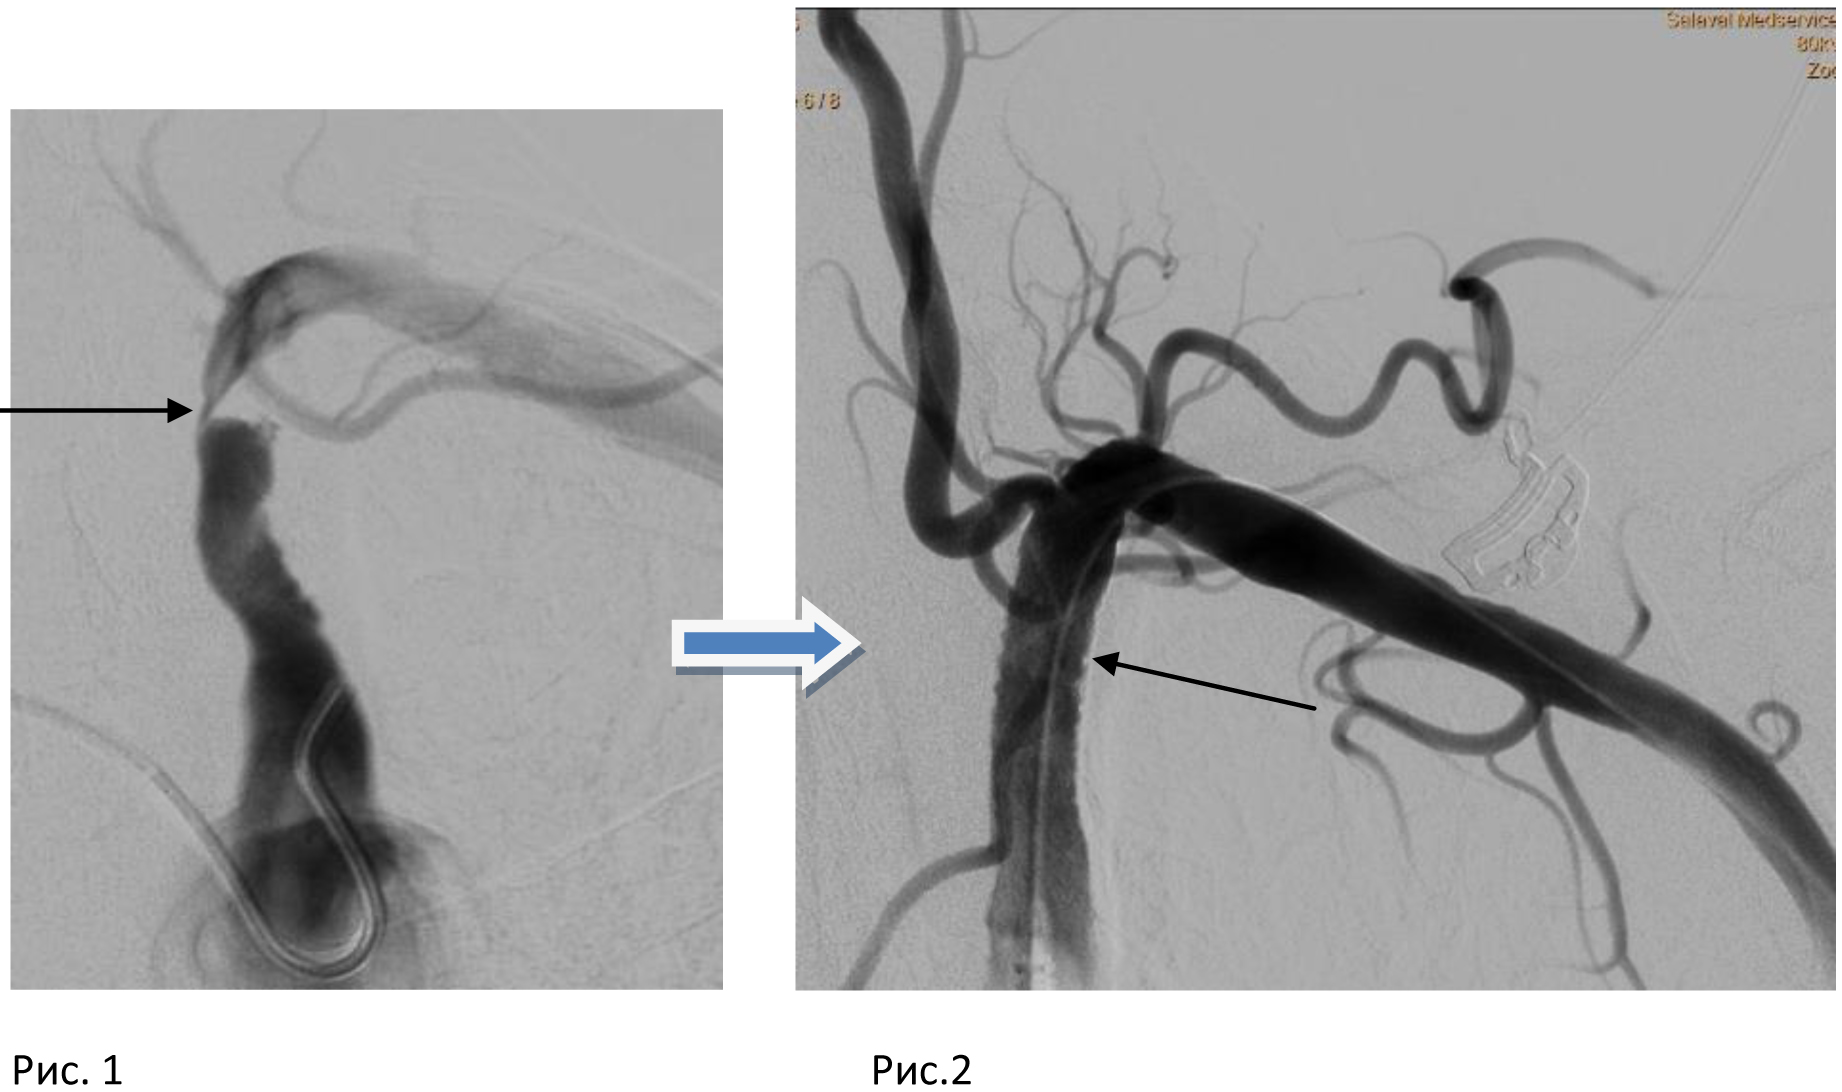

Пациентка с жалобами слабость в левой руке, усиливающиеся при выполнении минимальной физической нагрузки, зябкость пальцев левой кисти, эпизоды головокружения, головных болей. На момент измерения перед ангиографией, давление на правой руке 190/100, на левой – 110/75. Разница систолического давления между руками 80 мм! На ангиограмме –окклюзия (закупорка) левой подключичной артерии в начальном сегменте (рис.1 – ангиография со стороны аорты, рис.2 – ангиография со стороны левой руки). Вследствие полной закупорки подключичной артерии, кровоснабжение левой руки осуществлялось по аварийной схеме, в обход через головной мозг – по позвоночной артерии, то есть, происходило обкрадывание головного мозга.

С помощью специальных инструментов, для минимизации рисков вмешательства используя только местную анестезию и доступ только через сосуды верхних конечностей (!), удалось пройти закупоренный участок, расширить его и установить баллонорасширяемый стент (рис. 3).

Адекватный кровоток по подключичной артерии (а значит и осуществляемое по ней кровоснабжение левой руки и головного мозга) было полностью восстановлено. Восстановив физиологическое направление кровотока, обкрадывание головного мозга было устранено. При контрольном измерении давления – разницы давления между руками больше нет.